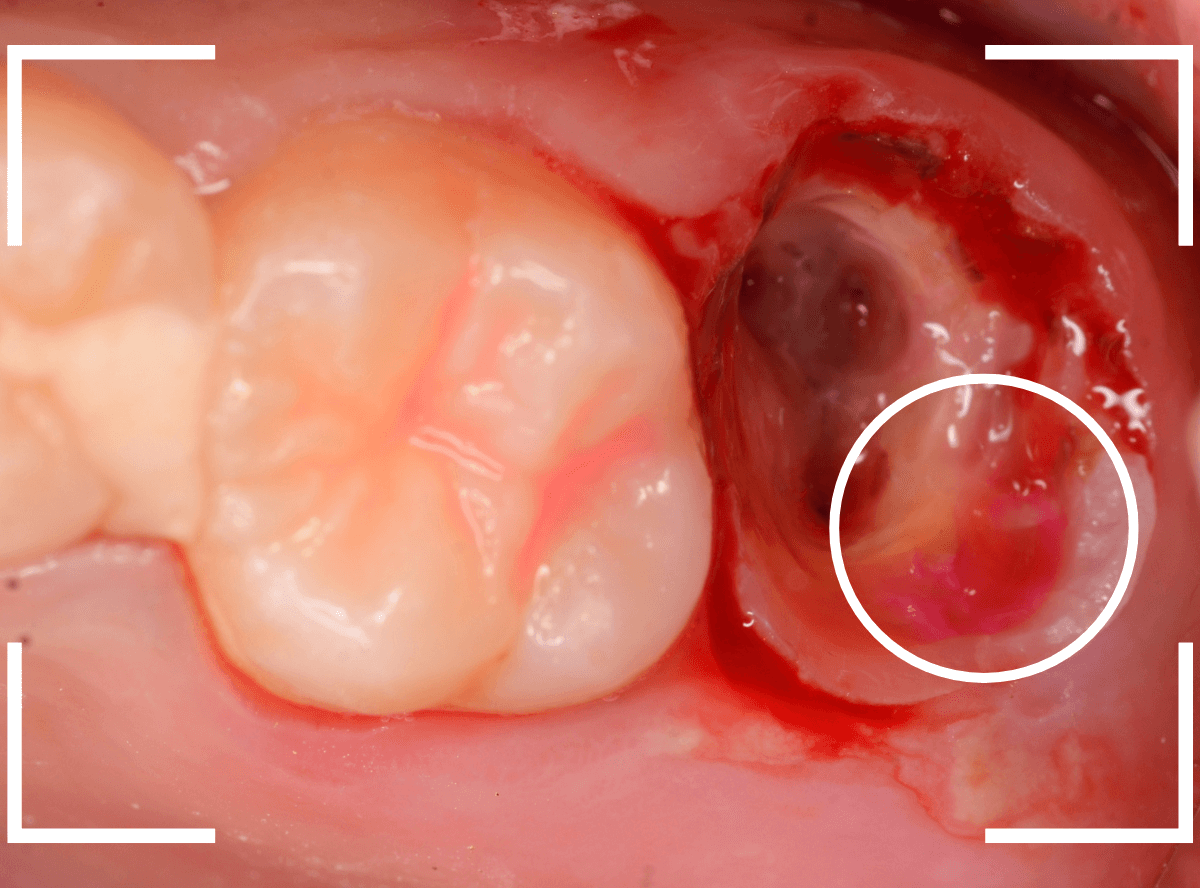

すると、土台の中で虫歯にもなっていました。

(〇部の赤い部分)

こういった事は、レントゲン写真でもよくわからない事が多く、土台を外す治療は本当に神経を使います。

今回は、歯肉の中まで歯が欠損しているので、このまま土台とさし歯を作り直しても、いい結果にはなりません。

患者さんに状況を説明し、歯の周りの歯肉を麻酔をして電気メスでトリミングします。

このように歯の際が歯肉からしっかり出てる状況で製作しないと、さし歯はしっかりお口の中で安定しません。